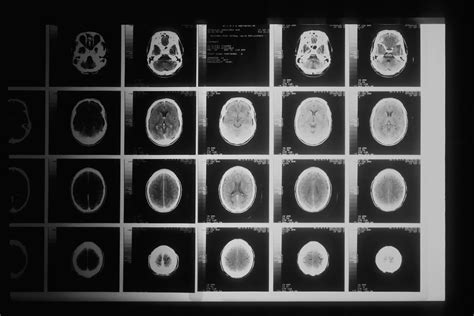

To understand why the turnaround time varies, it is helpful to know what happens to your data after you leave the scanning room. Once the CT scanner captures the images, they are digitally transmitted to a radiologist’s workstation. A radiologist is a medical doctor who specializes in diagnosing diseases using imaging technology. They do not just "look" at the pictures; they conduct a systematic analysis of hundreds, sometimes thousands, of individual "slices" or cross-sectional images to identify abnormalities, assess organ health, and correlate findings with your clinical history.